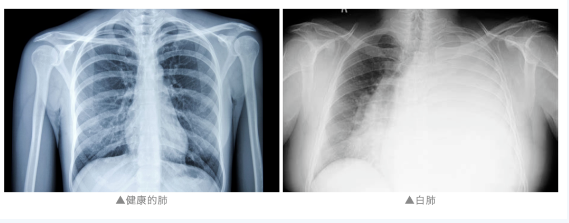

通常來說

“白肺”是指急性呼吸窘迫綜合征

主要發(fā)生在重癥感染時(shí)

雙肺彌漫性病變進(jìn)展迅速